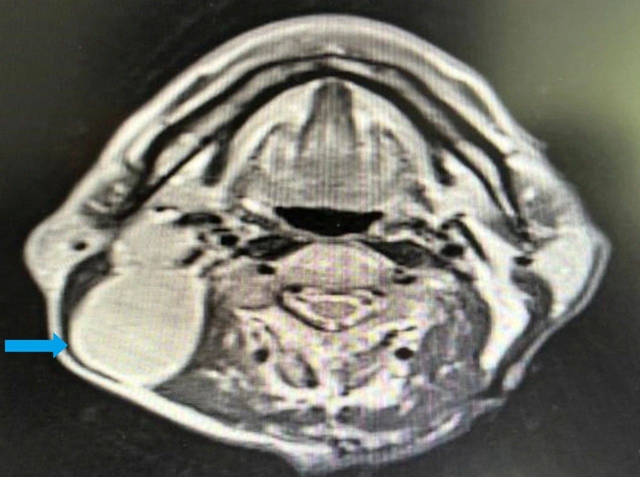

鼻咽部核磁共振:鼻咽部粘膜明显增厚(右侧为甚),鼻咽腔变窄,符合鼻咽癌变表现,双侧颈部多发淋巴结增大转移,右侧为多;

综合检查结果,西医诊断为:鼻咽部恶性肿瘤(分化型非角化性癌)侵及口咽、咽旁间隙伴咽后、颈部转移淋巴结;肺继发恶性肿瘤;中医诊断为鼻咽癌(痰瘀互结)。